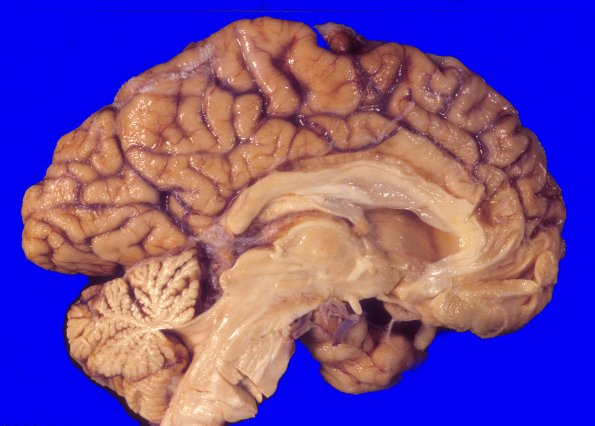

Washington University Experience | METABOLIC | Neuronal Ceroid Lipofuscinosis (NCL) | 11A1 NCL (Case 11)

At autopsy the weight of the unfixed half-brain is 670 gm (whole brain 1340g). There is modest global cerebral cortical atrophy and cerebellar vermal atrophy.